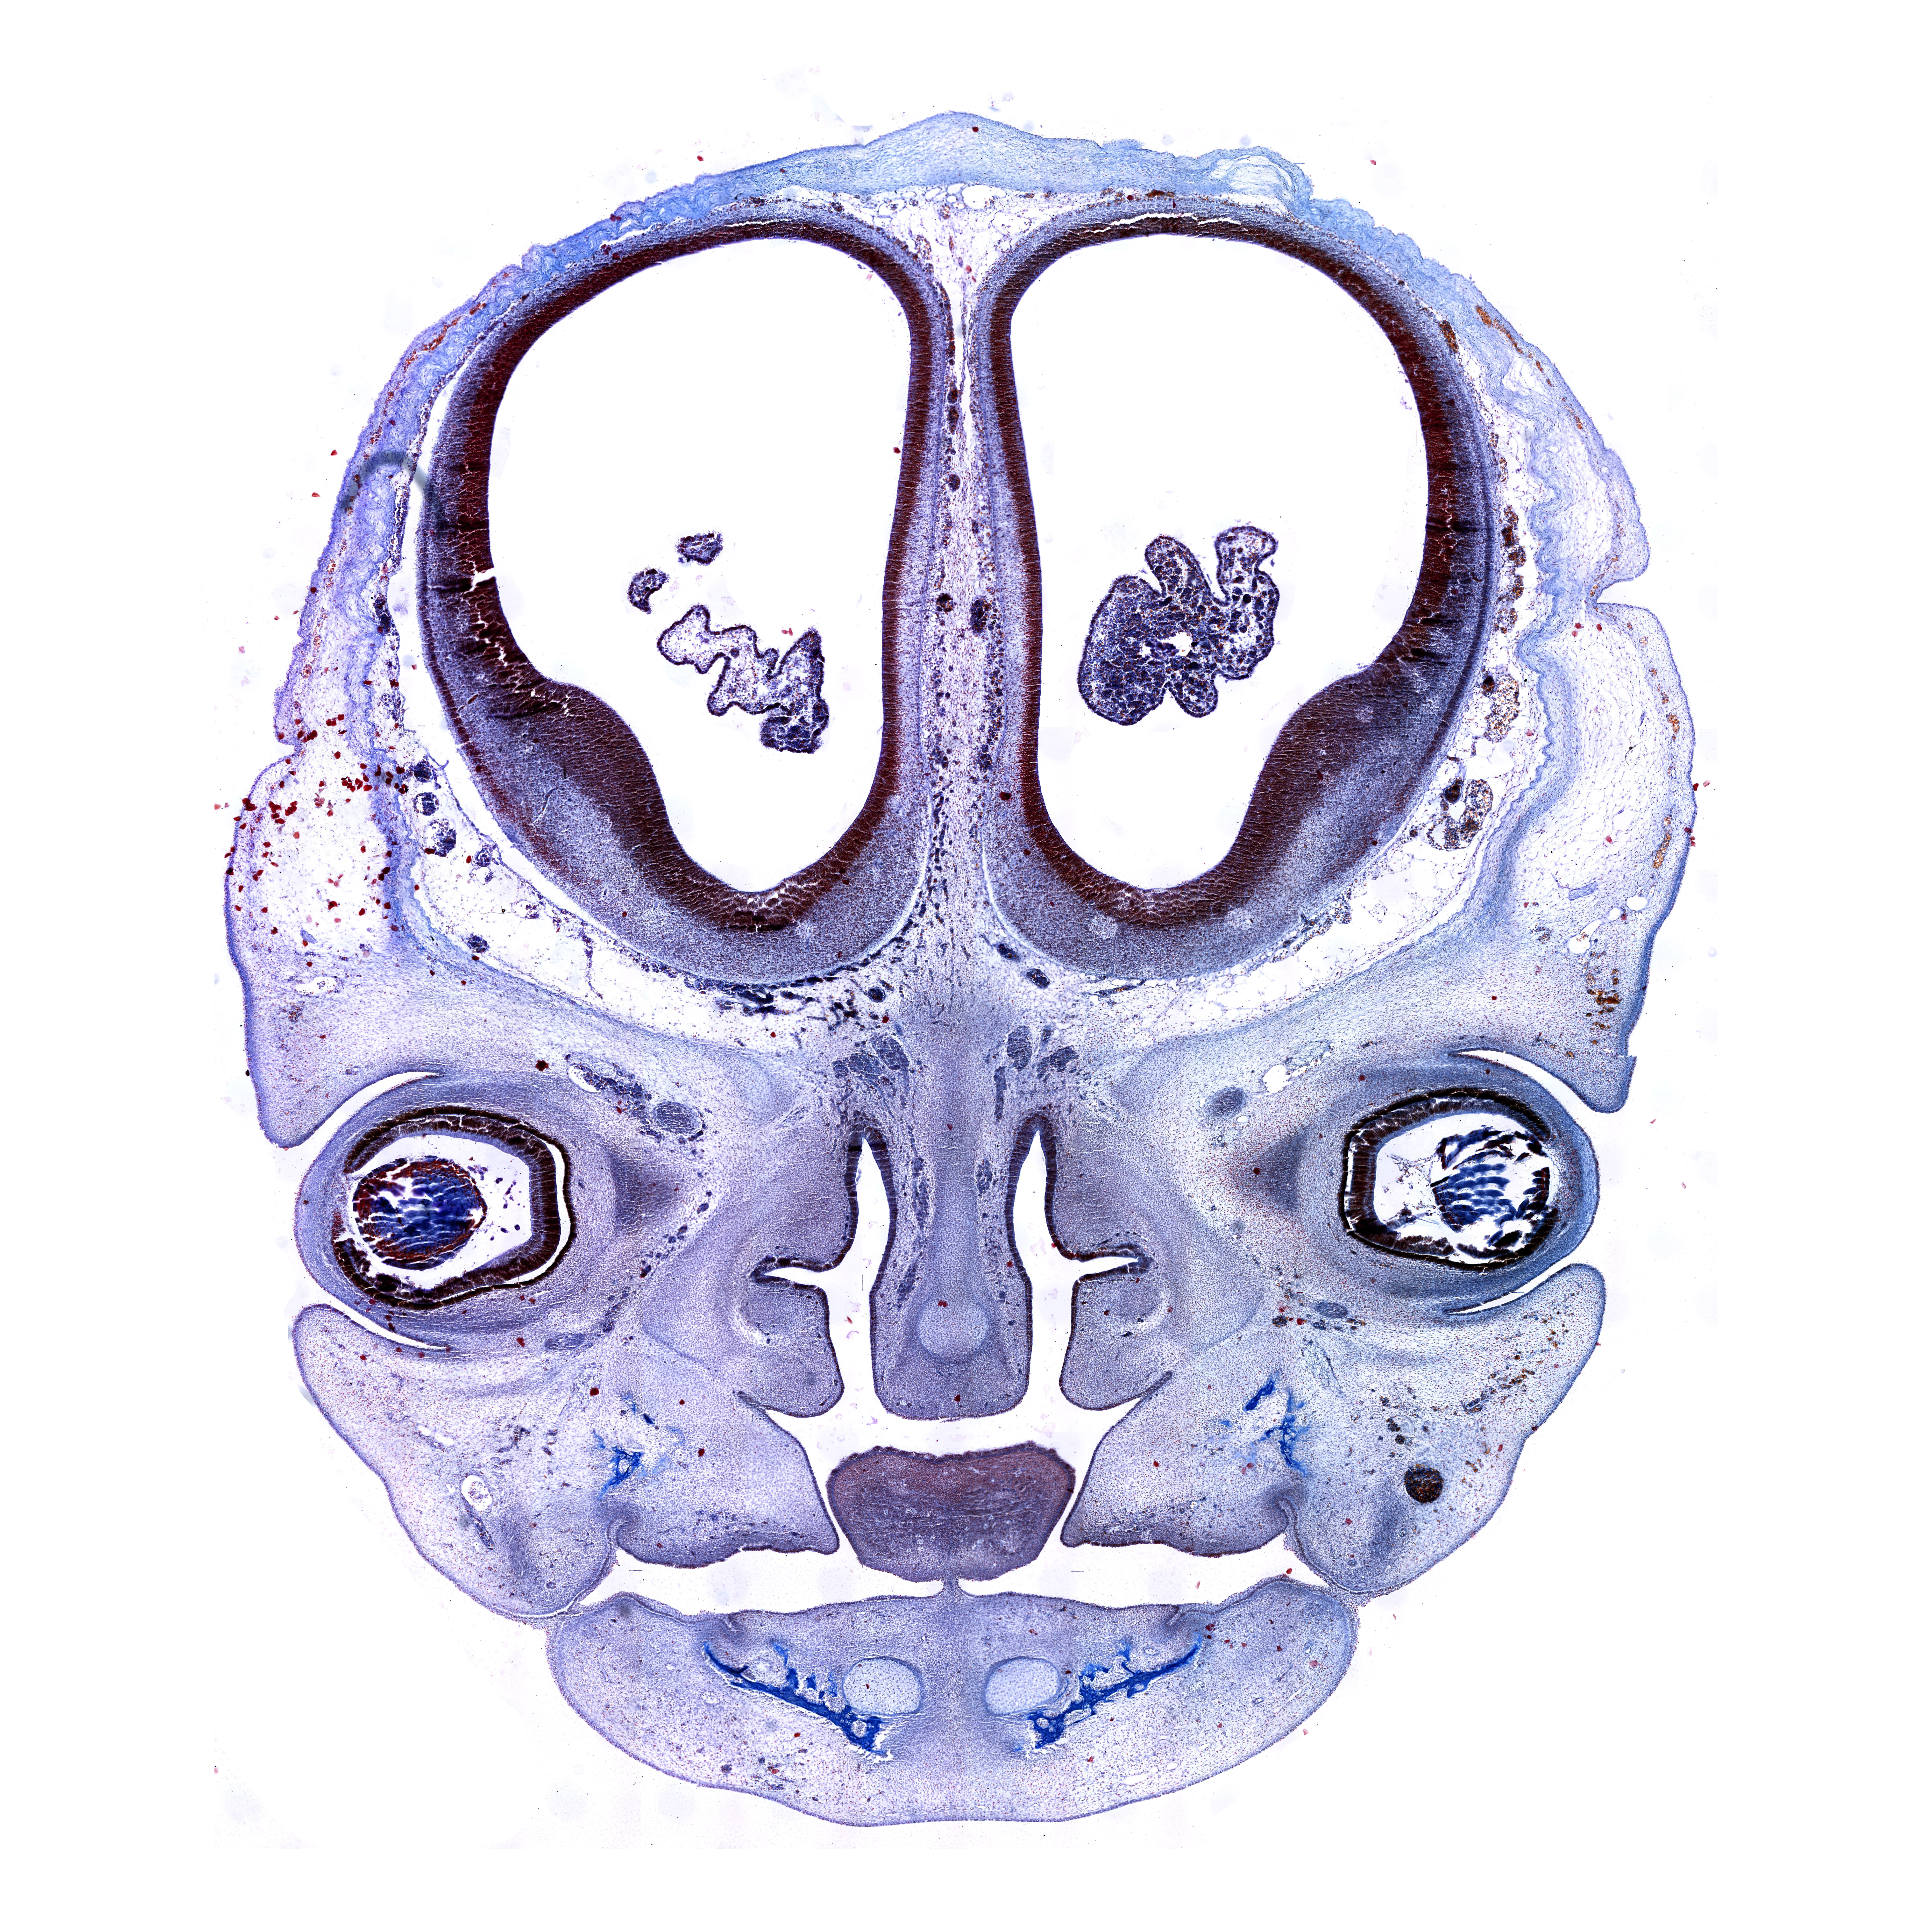

Human brain development atlas

10th gw

Mallory